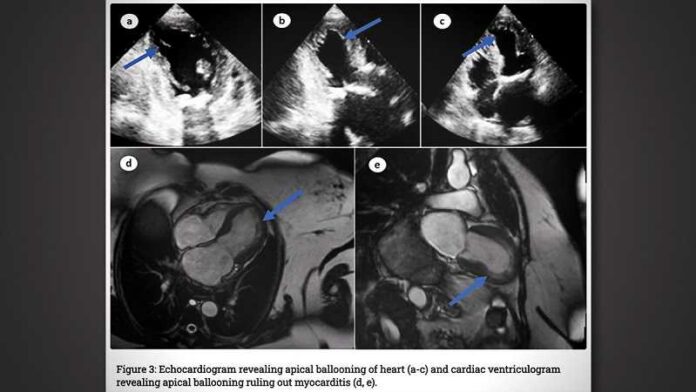

Tests op covid-19 bleven negatief. Een ECG en transthoracale echocardiografie toonden duidelijke afwijkingen in de hartfunctie, en de artsen vonden ook longoedeem op de röntgenfoto. De patiënte leed aan aanhoudende tachycardie en bloeddrukschommelingen. In de loop van de ziekte raakte ze in shock. Een longembolie en trombotische of obstructieve laesies in de kransslagaders konden worden uitgesloten, maar een MRI liet een duidelijke ballonvorming van het hart zien, maar geen myocarditis. Op basis hiervan en van de eerdere coronavaccinatie stelden de artsen de diagnose TCM – er kon geen andere oorzaak voor de ernstige hartklachten gevonden worden.